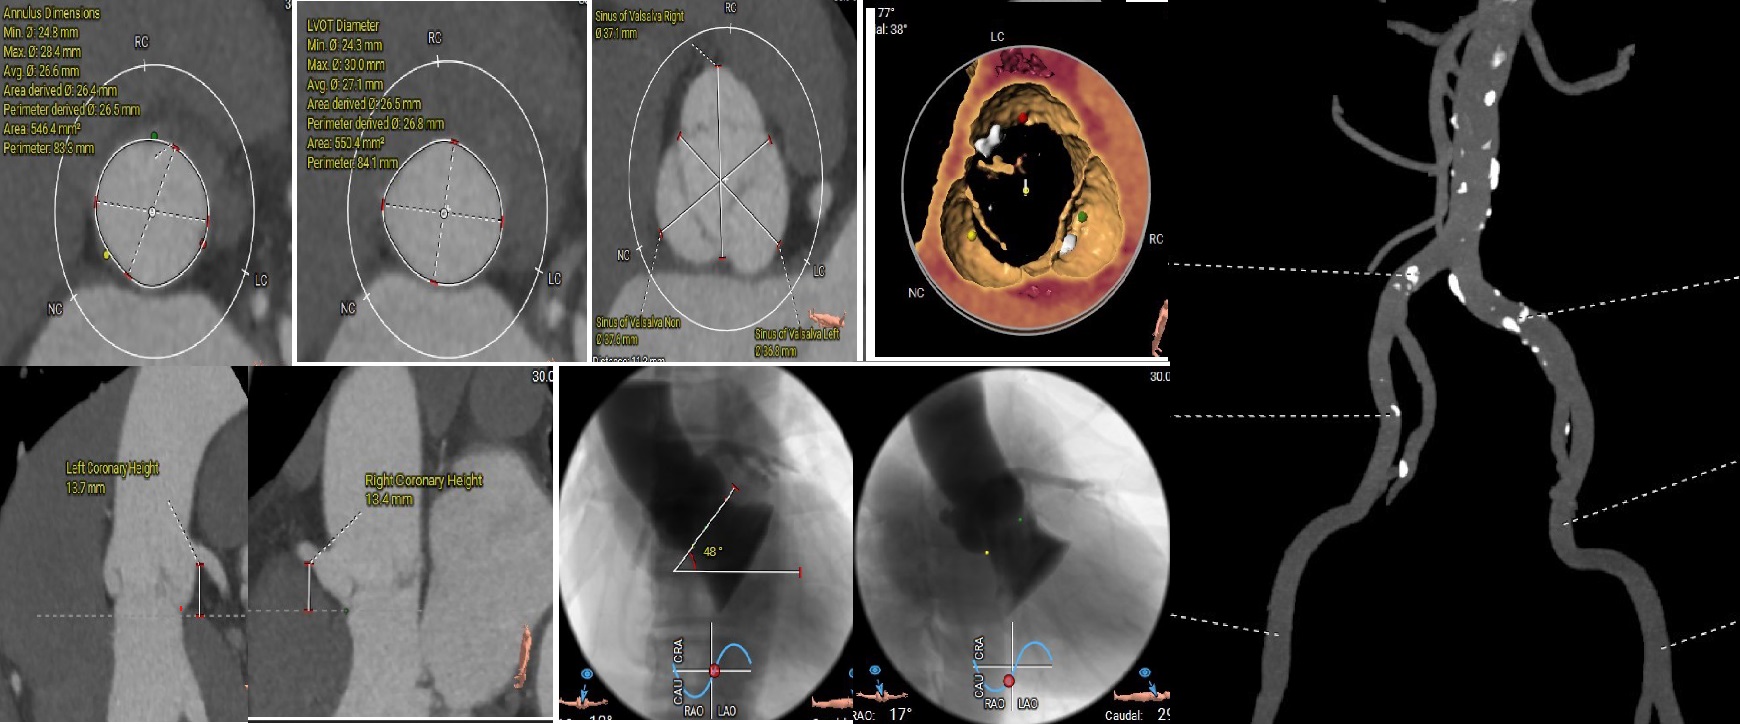

TTE was suggestive of valvular heart disease with severe AR, mild MR and severe TR with chordae rupture and prolapse of anterior leaflet of the tricuspid valve. TEE showed bi-atrial enlargement, left ventricular dilatation with diastolic dimension of 70mm. Left ventricular function was normal with ejection fraction of 70%. Aortic valve was thickened with no calcification of leaflets. Tricuspid annulus dimension measured 47mm, coaptation gap was 4.6mm with regurgitation volume of 65 ml.

Based on the CTA, 30mm VitaFlow™ system self-expanding valve was decided with oversizing of 20%. Coronary angiogram showed no coronary artery stenosis. Risk analysis showed high risk with Euroscore II of 27%. Multi-disclipinary team decided that a single stage percutaneous transcatheter approach would be the optimal treatment option for addressing the AR and TR. Tricuspid TEER followed by TAVI was decided to avoid interference of temporary pacemaker wire during clip deployment.

First, through the right femoral vein, the Neoblazar® delivery system (Dawneo Neoblazar, Hangzhou, China) was advanced till the tricuspid valve, and two clips (TMrCLAMP-S) were deployed to grasp the anterior and septal leaflets with a desired outcome reducing to a mild residual TR. Postoperative VC width was 0.2cm with EROA of 0.17cm2 and regurgitation volume of 15mL. The delivery system removed and 18 fr sheath exchanged. A 5 fr temporary pacemaker wire positioned through sheath into the right ventricle. Subsequently, the right and left femoral arteries were each accessed with 6-fr sheath and 22 fr sheath respectively. Through the left femoral artery, the TAVI delivery system with a 30mm VitaFlow Liberty™ self-expanding valve system (MicroPort®, Shanghai, China) was advanced across the aortic valve and deployed under transoesophageal and fluoroscopic guidance with rapid ventricular pacing at 140 beats/minute and pacing slowly tapered. The mean valvular gradient after TAVI decreased to 6 mmHg. Then, percutaneous access closure of arterial access was achieved using a pre-closure technique with the suture-mediated ProGlide device (Abbott Laboratories Inc., Chicago, Illinois, United States). The total procedure time was 60min. There were no intraoperative complications. The temporary pacemaker was removed two days later. Predischarge transthoracic echocardiogram showed a normal functioning aortic THV with a mean gradient of 6mmHg and mild residual tricuspid regurgitation.